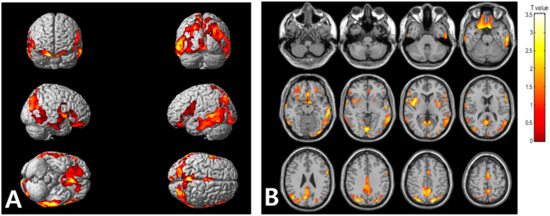

| Regions | Brodmann Area | Size | MNI Coordinates | T Value | p | ||

|---|---|---|---|---|---|---|---|

| X | Y | Z | |||||

| Right occipital lobe, lingual gyrus | BA 18 | 5896 | 2 | −84 | −8 | 3.56 | <0.001 |

| Right parietal lobe, precuneus | BA 19 | 26 | −80 | 42 | 3.52 | <0.001 | |

| Right parietal lobe, precuneus | BA 31 | 8 | −68 | 24 | 3.23 | 0.001 | |

| Right frontal lobe, precentral gyrus | BA 44 | 1315 | 62 | 8 | 4 | 3.55 | <0.001 |

| Right temporal lobe, middle temporal gyrus | BA 21 | 64 | 0 | −8 | 3.35 | <0.001 | |

| Right insula | BA 13 | 36 | 10 | 4 | 3.31 | <0.001 | |

| Left parietal lobe, precuneus | BA 7 | 4022 | −18 | −78 | 48 | 3.54 | <0.001 |

| Left temporal lobe, inferior temporal gyrus | BA 20 | −62 | −28 | −16 | 3.44 | <0.001 | |

| Left occipital lobe, inferior occipital gyrus | BA 18 | −34 | −90 | −14 | 3.2 | 0.001 | |

| Left frontal lobe, rectal gyrus | BA 11 | 2258 | −8 | 10 | −24 | 3.37 | <0.001 |

| Right frontal lobe, inferior frontal gyrus | BA 47 | 26 | 12 | −22 | 3.28 | <0.001 | |

| Left frontal lobe, medial frontal gyrus | BA 25 | −6 | 6 | −16 | 3.26 | <0.001 | |

| Left frontal lobe, superior frontal gyrus | BA 6 | 348 | −2 | 4 | 54 | 3.3 | <0.001 |

| Left frontal lobe, medial frontal gyrus | BA 6 | −4 | −8 | 58 | 3.02 | 0.002 | |

| Left frontal lobe, inferior frontal gyrus | BA 44 | 450 | −60 | 8 | 18 | 3.17 | 0.001 |

| Left cerebrum, frontal lobe, precentral gyrus | BA 6 | −60 | 6 | 30 | 3.17 | 0.001 | |

| Left frontal lobe, inferior frontal gyrus | BA 45 | −56 | 20 | 12 | 3.07 | 0.002 | |